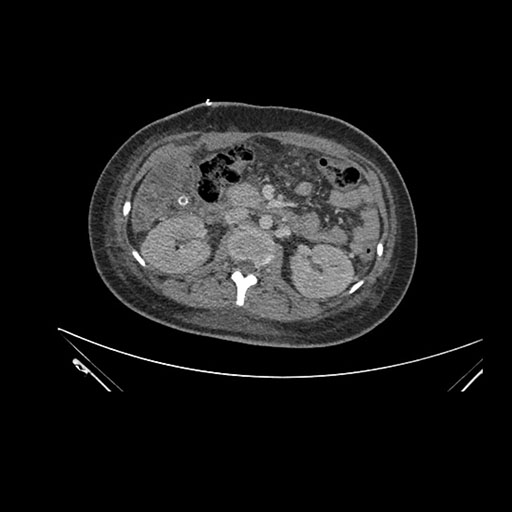

Axial Venous